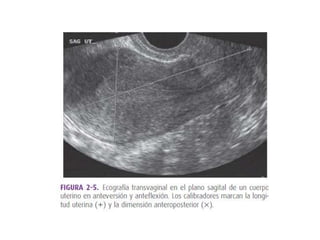

El ultrasonido transvaginal es un

método para captar imágenes del

aparato genital en las mujeres. Se

inserta una sonda manual directo a

la vagina. Se mueve la sonda dentro

de la cavidad vaginal para captar las

estructuras pélvicas a la vez que se

observan imágenes de ultrasonido

en un monitor. Esta prueba puede

realizarse para evaluar mujeres con

problemas de infertilidad, sangrado

anormal, fuentes de dolores

inexplicables, malformaciones

congénitas del útero y ovarios y

posibles tumores e infección

Uso de transductores de alta frecuencia con mejor resolución.

Exploración de pacientes que son incapaces de plenificar vejiga.

Exploración de pacientes obesas.

Evaluación de un útero en retroversión.

Mejor distinción entre masas anexiales y asas intestinales.

Mayor detalle de las características internas de una masa

pélvica.

Hallazgos abdominales inciertos.

Mejor caracterización de una lesión.

Fuerte historia familiar de Ca ovárico.

Sospecha de enfermedades endometriales.

Valoración de un útero en retroversión o en retroflexión.